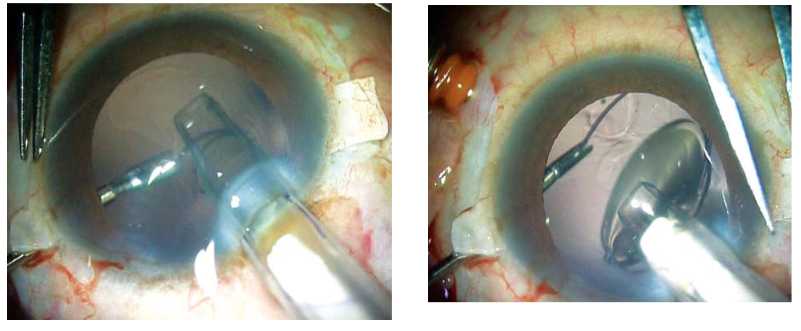

在IOL襻的理想出口处进行巩膜局部切除和电灼。插入灌注套管或前房维持器。如果使用灌注套管,可以使用23G无缝线的穿刺器和导管。灌注套管最好位于鼻下内侧象限,以防干扰巩膜瓣的制作。制作两个大约2.5mm×3 mm的巩膜瓣,对角相距180度(图 1A 和 B)。然后通过玻璃体腔或前路进行23G玻璃体切割术,以解除所有玻璃体牵拉。在巩膜瓣下,大约离角膜缘1.0mm处进行两个直的巩膜切口。然后制作一个透明的角膜/巩膜隧道切口以植入IOL。IOL植入时,术者一手使用McPherson钳,另一手使用23G/25G的夹持钳(Micro Surgical Technology, USA)通过下方巩膜切口。可以使用任何末端开口的镊子,夹住IOL襻的尖端,沿着襻的曲线穿过下方的巩膜切口并将其拉出(图2A和B),使其在下方巩膜瓣下露出。同样,通过巩膜瓣下的上方巩膜切口,也可以将襻的尾端露出。如果制作的是巩膜隧道切口,用10-0单丝尼龙线缝合切口。然后将襻的尖端塞入用26G针制作的巩膜隧道的延伸点中。用纤维蛋白胶闭合巩膜瓣(图3A和图B)。移除前房维持器或灌注套管。结膜也用相同的纤维蛋白胶闭合(图4)。

图2A和B:图示在巩膜瓣下用22G针头进行巩膜切开。用25G镊子将IOL襻暴露。